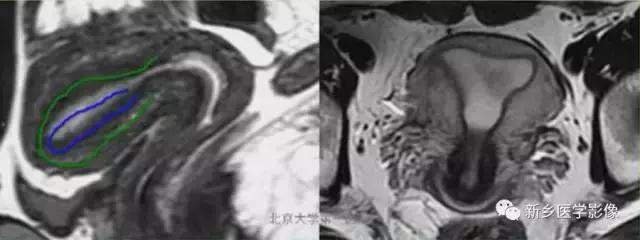

II:单角子宫:

子宫单角,呈香焦形。伴或不伴残角,残角体积小,可存在内膜腔,可同外界相通。

上图:单角子宫(II-B残角,有内膜腔,不相通):右侧残角宫腔内积血,为短T1长T2异常信号。左侧单角子宫,见带状结构,呈香蕉样。

上图:II-D无残角:右侧单角子宫,左侧无残角